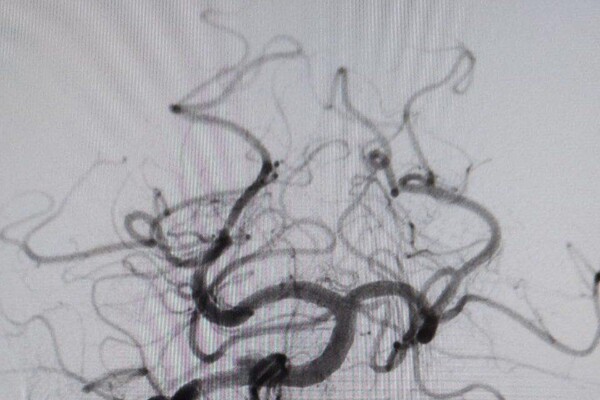

«В ходе обследования врачи диагностировали закупорку основной артерии, обеспечивающий кровоснабжение важнейших отделов головного мозга. Это очень тяжелое состояние с крайне высокой летальностью», — пояснили врачи.

Мужчине провели экстренную операцию, в ходе которой удалили тромб и установили стент.